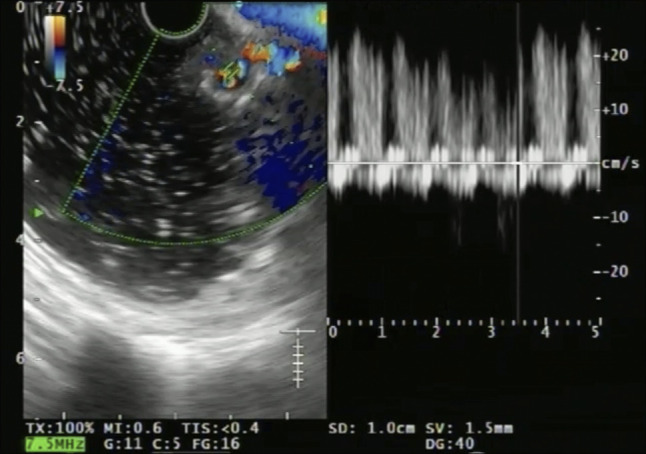

Expanding Horizons of Vascular Interventions: Endoscopic Ultrasound-Guided Angioembolization for a Refractory Upper Gastrointestinal Bleed From a Gastric Dieulafoy Lesion.